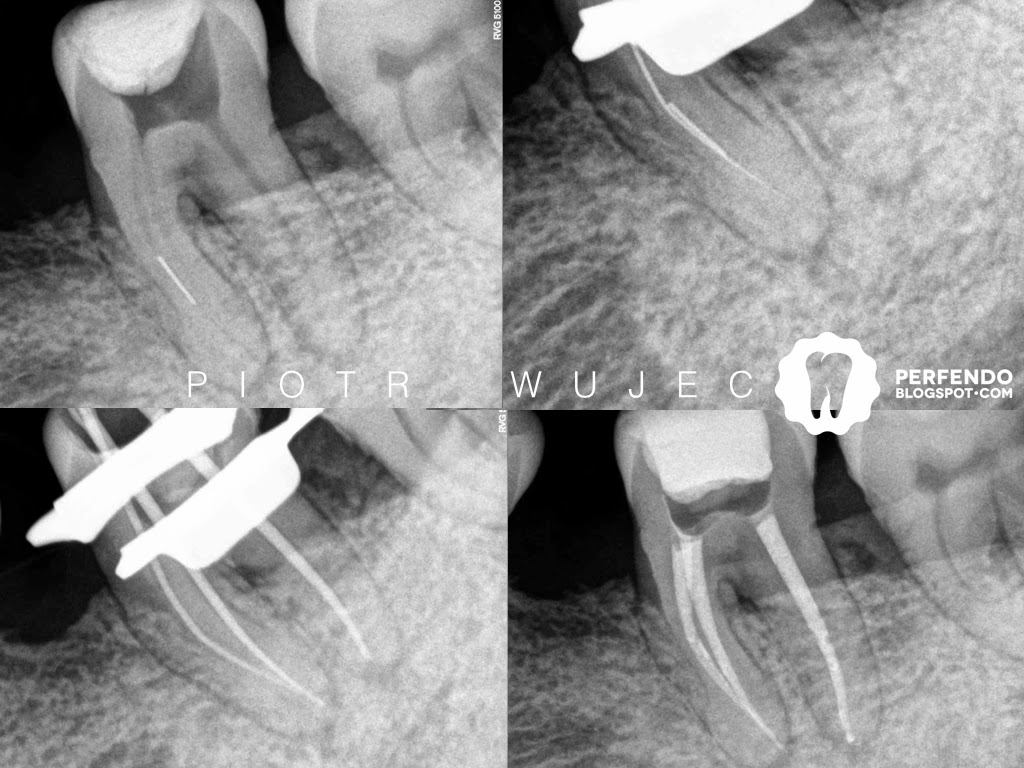

This patient was sent to my office with a lot of troubles. Tooth 46 was not one of them at the beginning. First Xray shows initial situation - tooth was root canal treated few years before. Distal canal was underfilled, mesial canals were shaped to small size, but no symptoms occurred that time. There was only small radiolucency surrounding mesial root, so we decided to wait and control that situation. 2 yrs later everything was fine. 3 yrs later patient start to complain about tenderness to percussion. On Xray we can see slightly bigger lesions nearby medial root, no lesions in distal. That was "green light" for as to do rendo. The hardest part was to find the lumen of distal canal - it was obliterated by dentine. Only last 2,5 mm was negotiable. Now we will prepare composite overlay, and wait for recall. ///// Ten pacjent trafił do mojego gabinetu z wieloma endodontycznymi problemami. Ząb 46 na tamtą chwilę nie był jednym z nich. Pierwsze zdjęcie pokazuje sytuacje wyjściową - ząb leczony kanałowo kilka lat wcześniej. Kanał dystalny był niedopełniony, kanały mezjalne były opracowane bardzo wąsko, ale ząb był zupełnie bezobjawowy. Na zdjęciu widoczna jest tylko nieznacznie poszerzona szpara ozębnej przy korzeniu mezjalnym, dlatego zdecydowaliśmy z pacjentem poczekać i obserwować tego zęba. Dwa lata później na wizycie kontrolnej wszystko było w porządku. Trzy lata później pacjent zaczął odczuwać dolegliwości bólowe na opukiwanie. Na zdjęciu rentgenowskim widoczne lekko powiększone zmiany przy korzeniu mezjalnym, brak zmian przy dystalnym. Ta sytuacja to "zielone światło" dla nas, by zacząć powtórne leczenie kanałowe. Najtrudniej było udrożnić kanał dystalny - był całkowicie zarośnięty zębiną. Tylko ostatnie 2,5 mm kanału było drożne. Pacjenta czeka rekonstrukcja protetyczna przy pomocy overleya kompozytowego i wizyty kontrolne.